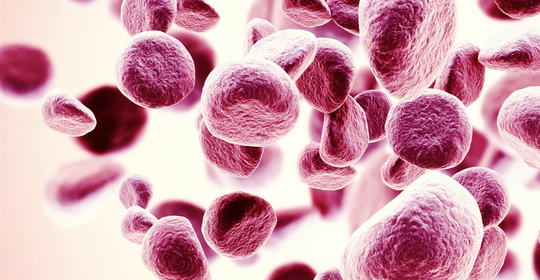

新生兒肺炎:成因、典型症狀與治療要點